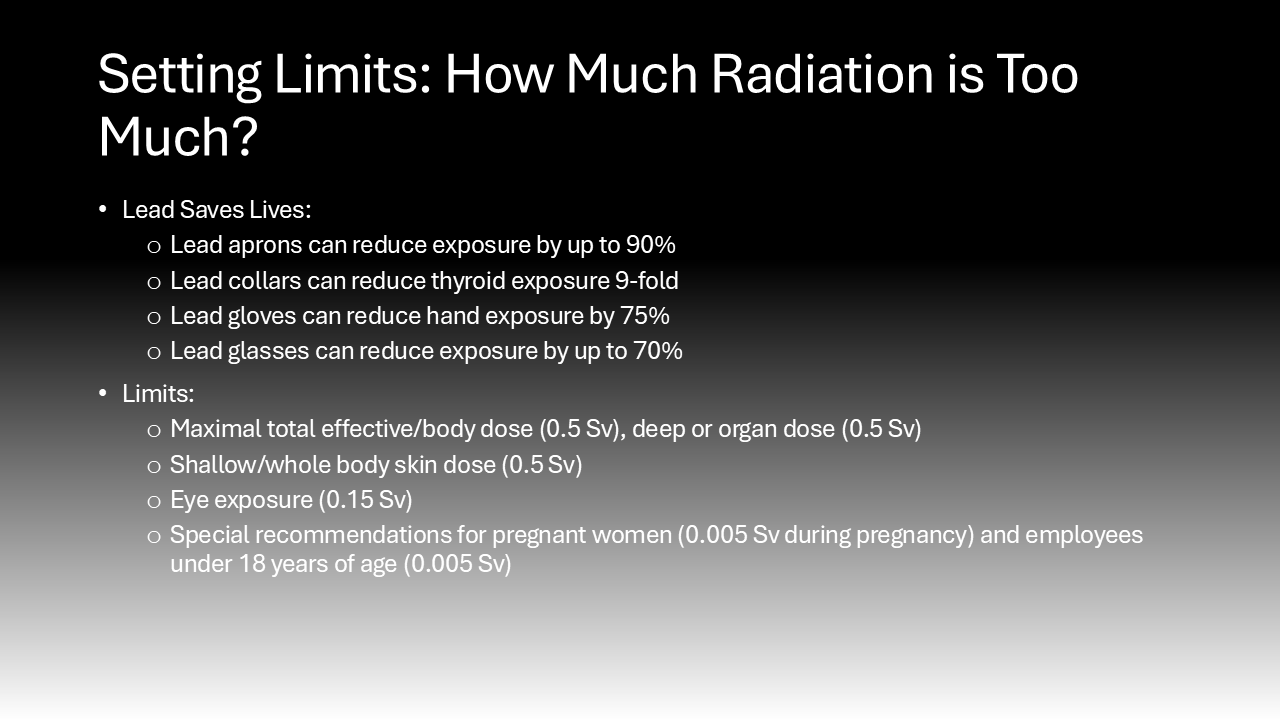

In the operating room, the core tenet of risk mitigation from intraoperative radiation exposure is known as “ALARA,” as low as reasonably achievable.6 This means surgeons are encouraged to use the lowest amount of radiation to achieve a safe surgical environment and outcome.6 To achieve ALARA, it is essential that surgeons wear dosimeters while in the OR to quantify their radiation exposure so it can be tracked by hospital occupational safety experts.15 Understanding their exposure is essential to alert them to their increased risk so they can accordingly mitigate radiation exposure. Many organizations and institutions set dose limits for radiation exposure for their physicians. For instance, the Cleaveland Clinic, a leader in the medical field sets the following annual limits of radiation exposure for their physicians: a maximal total effective/body dose (0.5 Sv), deep or organ dose (0.5 Sv), shallow/whole body skin dose (0.5 Sv), eye exposure (0.15 Sv), and special recommendations for pregnant women (0.005 Sv during pregnancy) and employees under 18 years of age (0.005 Sv).6

Behavioral modifications and personal protective equipment also play a key role in risk mitigation for those exposed to intraoperative radiation.4 When surgeons stand further away from the radiation source, they are exposed to an inversely proportionally decreased dose of radiation.4 Additionally, simply standing on the same side as the receiver significantly reduces the exposure to the scattering radiation as it bounces off the receiver.4 Following the establishment of the Advisory Committees on X-Ray and Radium Protection in the late 1920s, recommendations and regulations requiring the availability and use of lead protection devices and shielding devices have significantly curbed the negative effects of intraoperative scatter radiation exposure.16 These policies were adopted by the Occupational Health and Safety Administration (OSHA) and local hospitals, such as Stony Brook University Hospital.17–20 Lead aprons can reduce exposure by up to 90%, lead collars can reduce thyroid exposure 9-fold, lead gloves can reduce hand exposure by 75%, lead glasses can reduce exposure by up to 70%, and shields can offer significant reductions.4,21